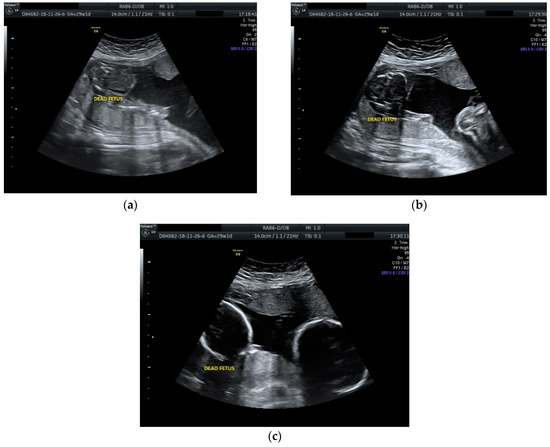

The case was managed conservatively with regular monitoring of the maternal coagulation profile, along with intensive fetal surveillance for the surviving twin (Figure 2 and Figure 3).

Figure 3.

Ultrasound scan performed at 31 weeks and 2 days of gestation: (a), (b), (c) dead fetus with consistent plastic changes along with normal growing fetus with normal amniotic fluid.